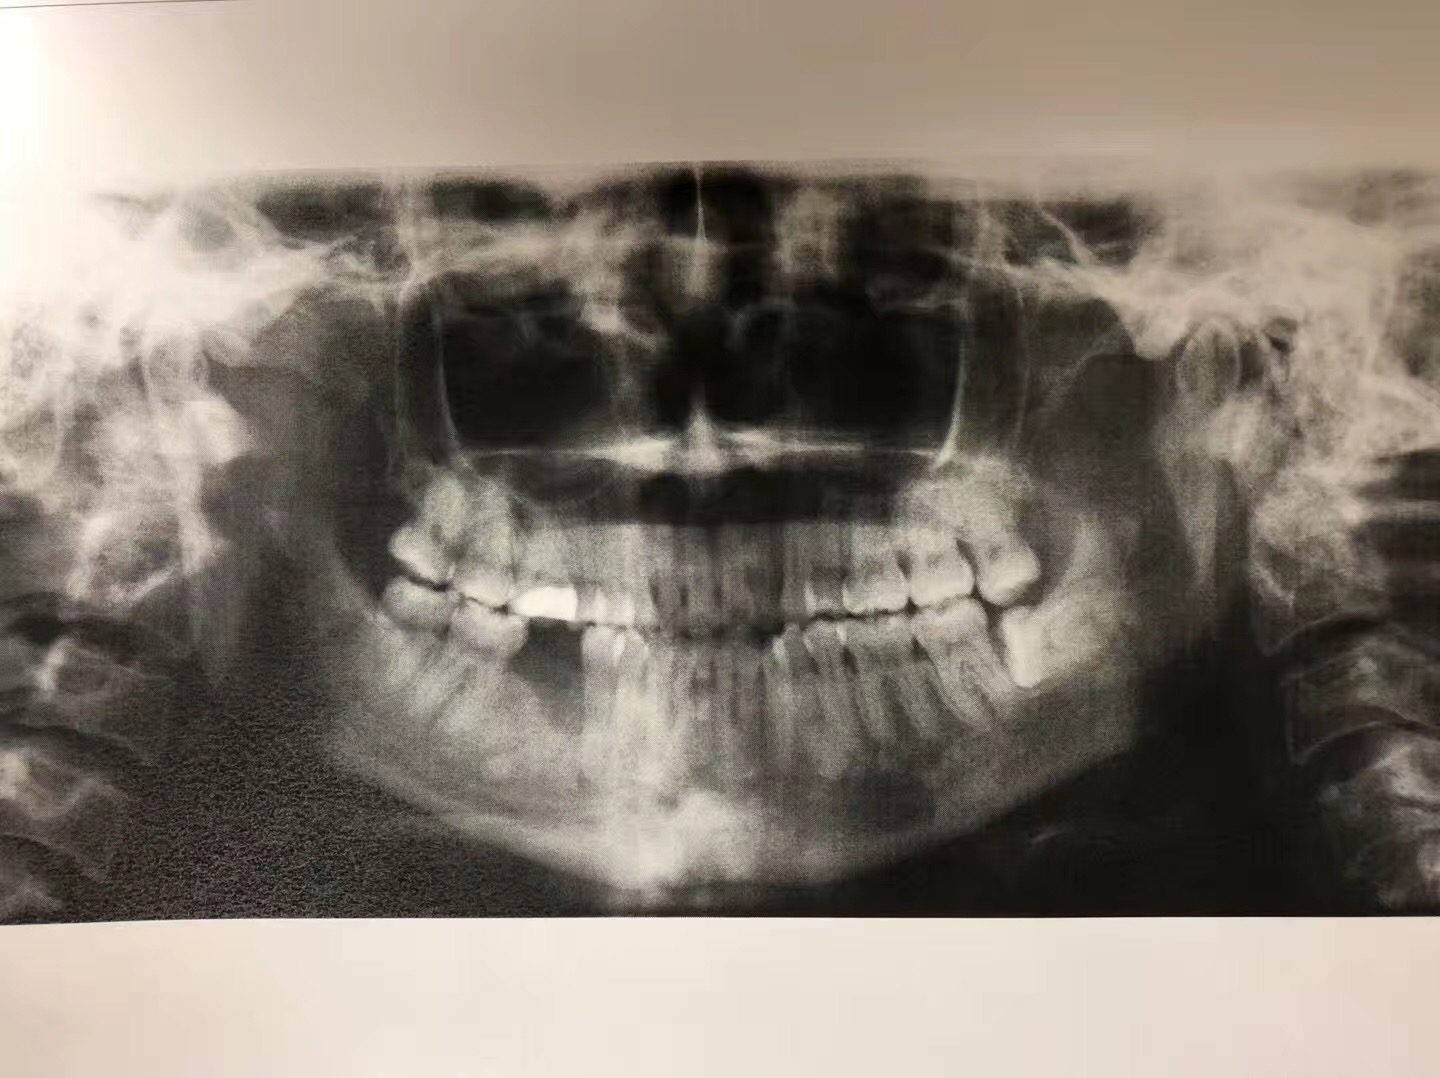

我是林俊男牙醫博士。今天讲述的是一位墨西哥裔年仅37岁乳腺癌第四期患者的实例,也就是说她的病情已经轉移到腦部和骨頭。

她从2011年患病到現在,一直在注射化療藥物(IV Zometa)。由于大多数癌症病人在接受静脉注射二磷酸盐药物帕米膦酸钠和唑来磷酸之后,使用了二磷酸盐治疗的患者可能会发生一种严重的下颌骨不良反应,称为下颌骨坏死。

2016年,她感觉第一大臼齒的地方很疼痛去看了一般的牙醫,这位牙醫立即幫她拔了疼痛的牙齒,结果她的牙根却留在牙糟裏。后來,她来到我們南加大醫院的口腔外科,我的住院醫生见状,幫她把牙根拔了,結果引起骨壞死。这一年多来,住院醫生只有開消炎藥和漱口水給她,但一直未见好转,后来,住院醫生把这位患者病情告诉我,希望我能幫她。我了解病情后,若按照常规治疗,效果不明显。我采用了自己研發的新藥,第一次病人需要在诊所注射,之後,再把藥交給病人,譲病人携帶回家自己打。二個星期後,病人回診,骨頭已經好了,而且還長的和之前一样。她见到我激动的说,林医生是我的救命恩人。